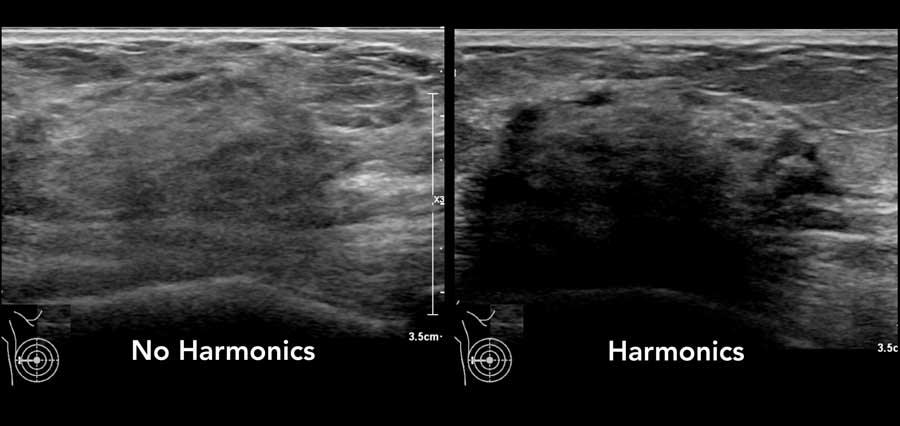

Chế độ hài âm (Harmonics)

Tạo ảnh hài âm là một kỹ thuật siêu âm khai thác đặc tính cộng hưởng của mô.

Kỹ thuật này còn được gọi là tạo ảnh hài âm mô (tissue harmonic imaging – THI).

Nếu máy siêu âm của bạn có tính năng này, bạn sẽ nhận thấy rằng hình ảnh thu được với chế độ hài âm có độ phân giải cao hơn và ít xảo ảnh hơn so với siêu âm thông thường.

Bóng cản phía sau có thể được tăng cường rõ hơn.

Lưu ý rằng khối ung thư vú nhỏ này được quan sát rõ hơn khi sử dụng chế độ hài âm.

Có một khối giảm âm với quầng tăng âm xung quanh và bóng cản nhẹ phía sau. Hướng của khối u là thẳng đứng.

Bờ khối không rõ và hình dạng khối u không đều.

Đây là một trường hợp khó và không điển hình.

Khi nhìn vào hình ảnh bên trái, gần như không thể nhận ra khối u.

Hình ảnh trông gần giống như mô tuyến bình thường.

Tuy nhiên, trên lâm sàng sờ thấy một khối u, và khi quan sát hình ảnh với chế độ hài âm được bật, chúng ta có thể thấy bóng cản phía sau.

Trường hợp này được xác định là ung thư vú.

Nếu máy siêu âm của bạn có chế độ hài âm, tốt nhất nên quan sát cả hai chế độ có và không có hài âm trong những trường hợp không rõ ràng ngay từ đầu.